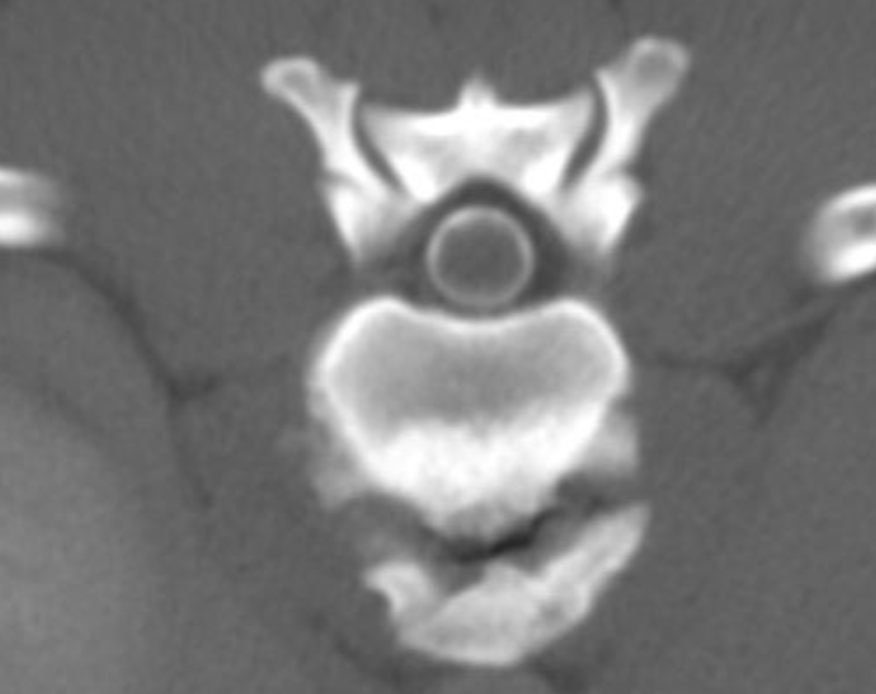

What is shown in these images?

left: normal CT right: bony stenosis